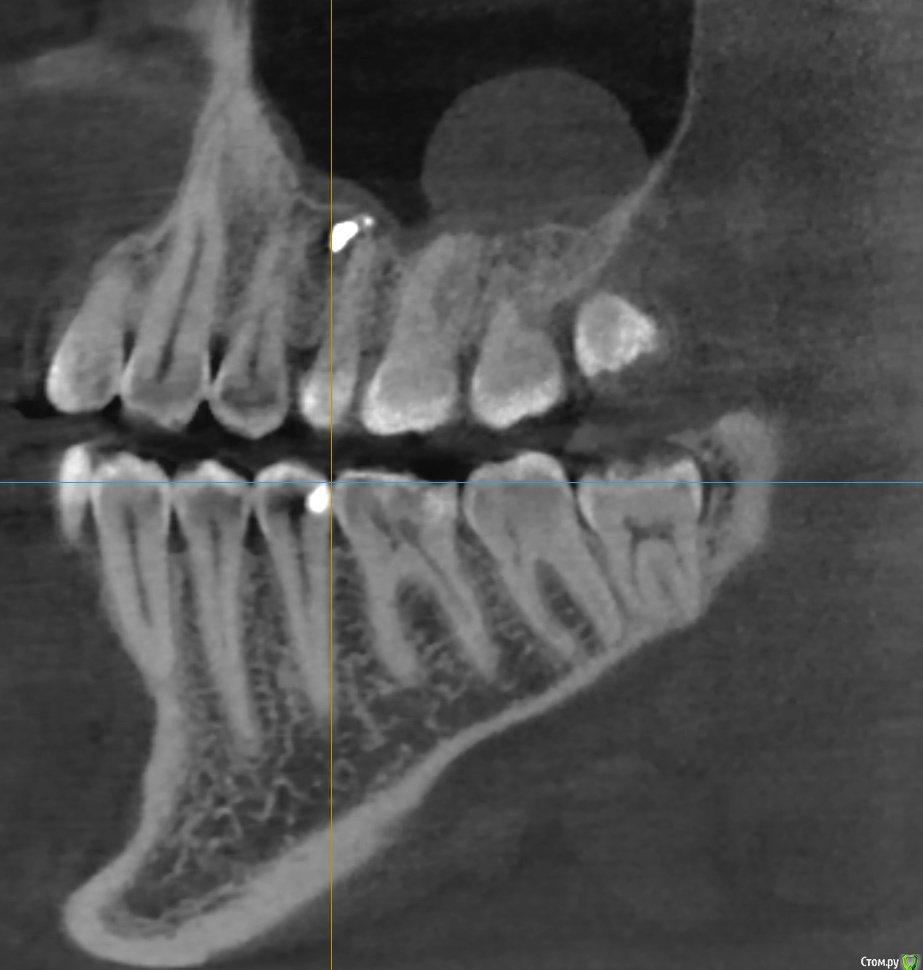

Bier Опубликовано 23 марта, 2018 Поделиться Опубликовано 23 марта, 2018 Если зубы витальные, то подобные образования в лечении не нуждаются. Определите живые ли зубы особенно 7й. Если да, то живите себе спокойно, если нет, то нужно пролечить каналы. У вас есть какая то проблема в области 4-5 зубов, срез КТ стоит нечетко и подробнее не ответить. Ссылка на комментарий

tmporaries Опубликовано 23 марта, 2018 Автор Поделиться Опубликовано 23 марта, 2018 Спасибо за ответы.Киста никак не беспокоит, обнаружили её случайно на КТ.5-ый зуб сверху был перелечен год назад. Ссылка на комментарий